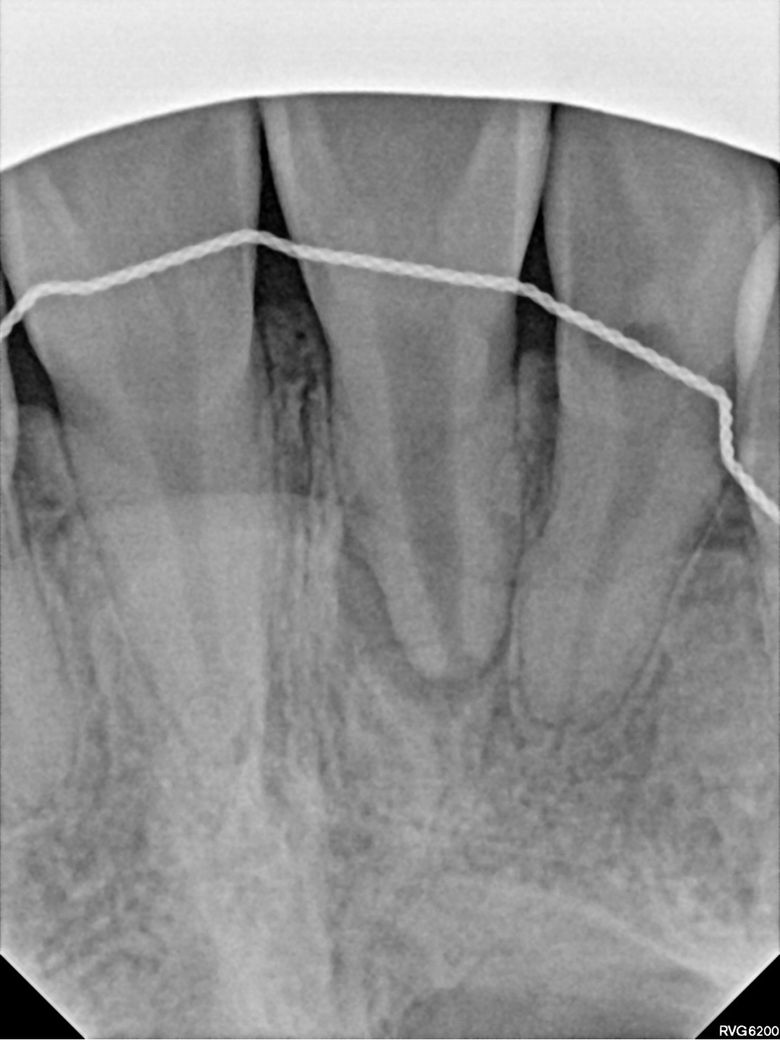

위에 쪽 앞니 하나 어금니 하나? 엑스레이 사진 찍어봤다는데 뭐가 뭔지 모르겠어서요 아마 첫번째 사진이 앞니같은데 신경치료 받아야할 정도인가요? 여기 선생님 말씀으로는 어금니는 충치가 좀 심해서 신경치료하고 크라운 씌워야한다 하셨고, 제 기준 오른쪽 앞니는 앞니 신경이 죽어있고 염증도 그래서 살짝 있다 육안으로 봤을 때도 앞니 두개 색상차이가 좀 난다 그래서 신경치료 몇회하고 크라운 해야한다 하셨는데 전 솔직히 거울 보면서 앞니 색상은 분간이 안돼서… 살면서 특별히 느낀 통증도 없었어요 참고로 신경 죽어있다는 앞니는 제가 정말 어렸을 때 깨진거고 그대로 두고 살다가 고등학생때 교정마치고 깨진부분 붙힌겁니다 세번째 사진 보시다시피 붙힌 라인에 노랗게 뭐가 낀거 마냥 변해있구요 일반 치아 마지막 사진은 윗니로 추정되는 것을 올리는 겁니다 제가 지금 윗니 교정장치가 떠서요 여기를 의심하는 건 아니고 다른 치과 의사분들 의견이 궁금합니다 추가질문 더더 하셔도 돼요 신경치료 무서워요… 대충 달지 말아주세요ㅠ 진지하게 봐주셨음 합니다

앞니의 경우에는 엑스레이 상으로 치아 뿌리끝에 염증이 있어 보입니다. 신경치료가 필요 할것같습니다. 어금니의 경우는 충치가 깊어 보이진 않습니다.

1. 신경이 괴사된 치아는 조금씩 검게 변하기도 합니다 앞니는 색 변색도 보이고, 탈구되었던 흔적도 보이네요 신경치료는 불가피할것 같습니다